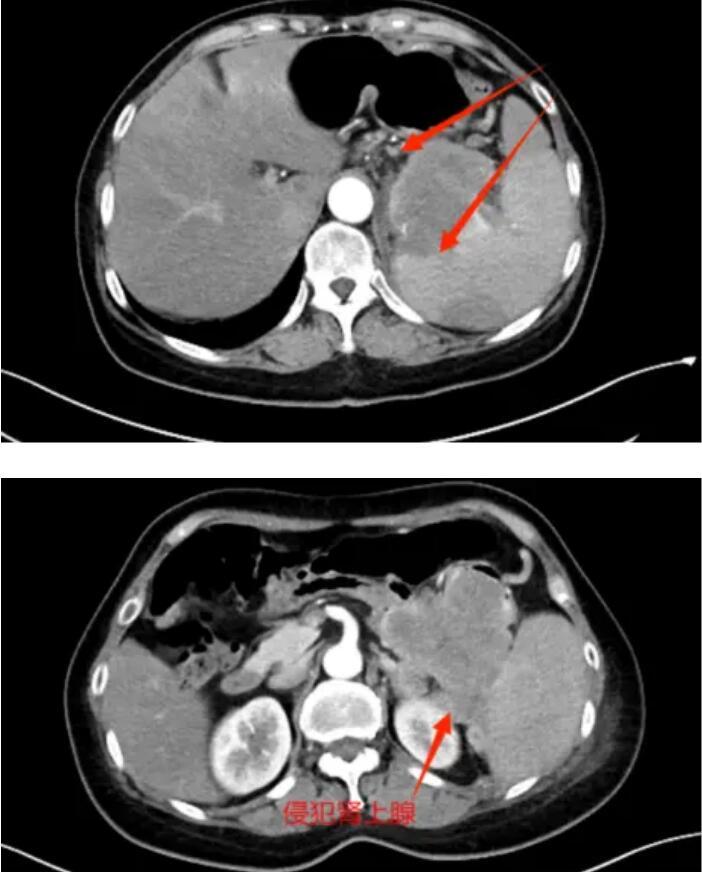

年过六旬的赵大娘(化名)近一月以来间断性出现左下腹疼痛,每次发作呈刺痛,伴食欲减退,排便困难,症状持续加重,门诊查CT回报:左上腹结肠占位性病变,考虑恶性,左肾上腺占位,考虑转移瘤可能(径线34mm*17mm),胃肠镜检查提示:“结肠肿物,结肠黏膜隆起”。赵女士家属拿到检查报告后心急如焚,经多方打听后,赵大娘来到了胃胰脾外科,希望得到救治。翟博教授经评估了患者影像资料后,考虑患者为胰腺体尾部的恶性肿瘤,并累及周围脏器。入院后的增强CT证实了上述诊断。

肿瘤侵犯脾及结肠、肾上腺

肿瘤侵犯结肠,肠管受压,造成患者排气排便困难

由于患者瘤体巨大,侵及周围脾、肾上腺、结肠、胃、十二指肠等多个脏器器官,手术难度极高,翟博教授随即请科室主任谭刚教授会诊,基于对患者病情分析及为降低手术风险,完善胰腺三维成像,得以精准定位肿瘤位置及周围血管分布,精准规划手术流程。